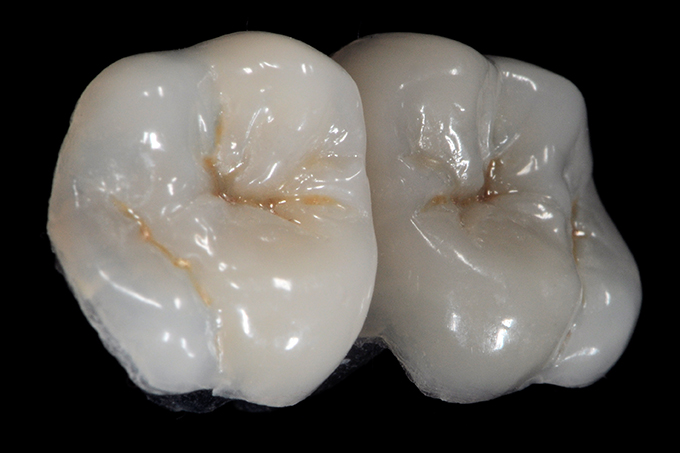

Occlusal anatomy

A different point of view which shows clearly the occlusal anatomy and the translucency effects.